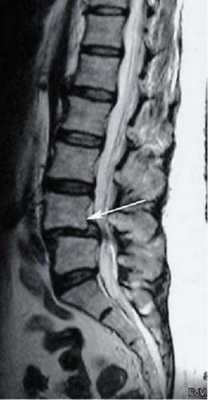

- Томографии. В случаях, когда ассимиляция атланта сопровождается симптомами поражения продолговатого мозга, необходимо исключение другой церебральной патологии: опухоли головного мозга, сирингомиелической кисты, абсцесса. С этой целью проводится КТ или МРТ головного мозга, которые в случае ассимиляции атланта могут выявлять признаки гидроцефалии. МРТ позвоночника позволяет судить о степени сдавления спинного мозга.

Основным инструментальным методом диагностики подвывиха шейных позвонков является рентгенография позвоночника с использованием как стандартных (боковой и прямой), так и дополнительных проекций: косых снимков, снимков через рот, рентгенограмм в положении разгибания и сгибания шеи. Перечень дополнительных проекций, назначаемых в каждом конкретном случае, определяется с учетом предположительного уровня повреждения. Наряду с рентгенографией могут быть назначены КТ и МРТ.

На КТ позвоночника выявляется уменьшение высоты диска и смещение суставных поверхностей, а при подвывихе С1 - асимметрия между атлантом и зубом. Проведение МРТ позвоночника позволяет уточнить состояние мягких тканей. Кроме того, пациентам с подозрением на подвывих позвонков назначают консультацию невролога для выявления возможных неврологических нарушений. При застарелых подвывихах и подозрении на ухудшение кровоснабжения головного мозга показана реоэнцефалография.